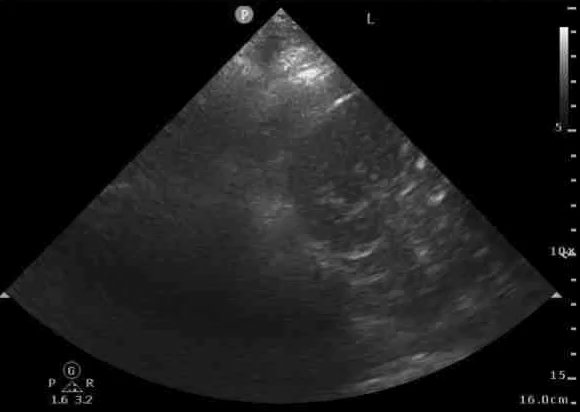

POCUS Image 5 - trying to get a better look at this structure above left hemidiaphragm

Right side, for comparison.